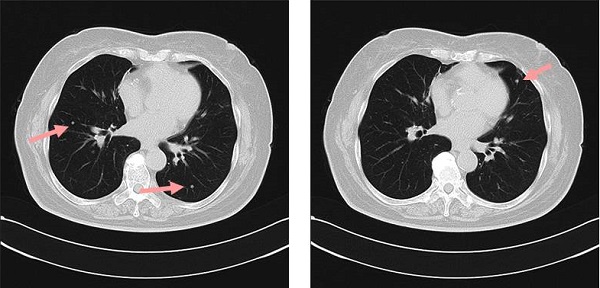

甲状腺乳頭癌の孤立性肺転移CT・PET-CT画像[Thorac Cancer. 2016 Mar;7(2):261-3.]

1cm程度の甲状腺乳頭癌・1cm 以下の甲状腺微小乳頭癌の肺転移は、片肺の孤立性結節のみです。しかもTBLB 組織診でサイログロブリン免疫染色も陰性のため、原発性肺癌との鑑別不可能です。当然、原発性肺癌として肺切除され、術中迅速病理診断で甲状腺乳頭癌肺転移が確定した時点で手術終了。

- 潜伏性(occult papillary thyroid carcinoma)だった[Thorac Cancer. 2016 Mar;7(2):261-3.][Nihon Naibunpi Gakkai Zasshi. 1991 Jun 20;67(6):655-65.]